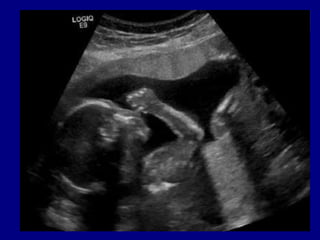

Obstétrico tardío (12 semanas en adelante)

Preparación para el ultrasonido

Imágenes Archivo PuntoScan

Preparación para elultrasonido • • • • • • • • • • Obstétrico tardío (12 semanas en adelante) Tiroideo Mama Testicular Transfontanelar Tejidos blandos Musculoesquelético Doppler Carotídeo Doppler venoso Doppler arterial

• 31.

Preparación para elultrasonido Imágenes Archivo PuntoScan